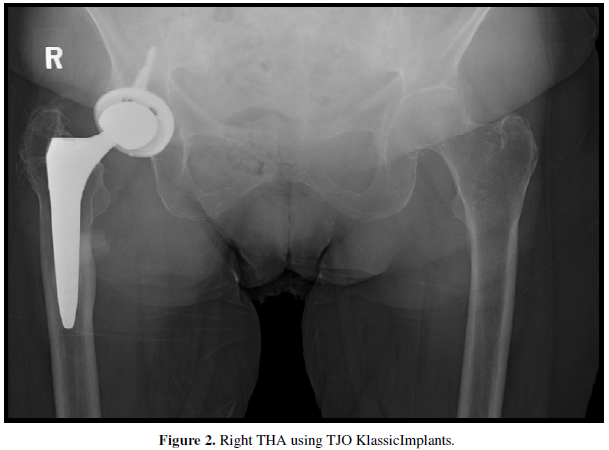

One patient with intractable psoas tendonitis, a 54-year-old female, underwent revision of the acetabular component 28 months after her initial implantation (Figure 2).